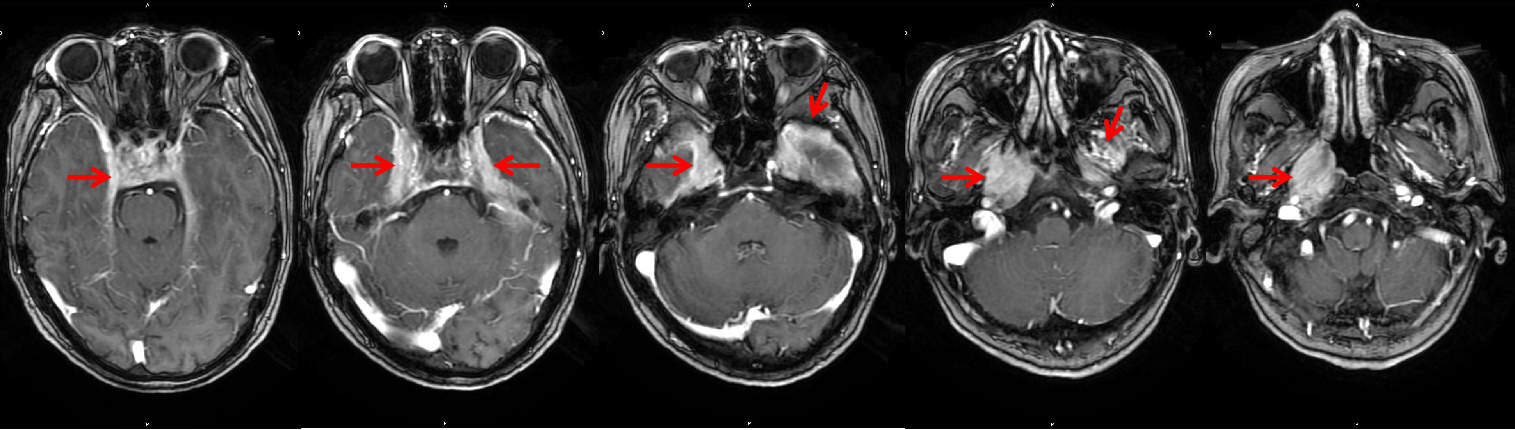

2022年4月底,我院放疗科接诊了一例在当地考虑为鼻咽癌拟行放疗的患者。该患者为女性,65岁,主因右侧头痛1月余,右面部麻木20余天、右眼视力下降伴右耳听力下降半月入院,且入院时合并有高钠血症、低钾血症、低蛋白血症等。MRI报告:1.鼻咽部右侧壁肿物,符合鼻咽癌表现。2.双侧海绵窦、中颅窝底、垂体柄及小脑幕脑膜弥漫性增厚(图1)。患者临床表现,如头痛、视力下降、听力下降等各种颅神经功能障碍,以及影像学上病变部位分布还是符合鼻咽癌表现的。五一假期将近,如果不诊断清楚抓紧定位、画靶区、放疗计划设计等放疗前准备工作,患者治疗可能因假日延后。放疗科在节前的全科查房中,认真梳理了患者所有资料、复阅影像,薛晓英教授认为,该患者MRI虽有鼻咽部异常信号并侵及颅内,结合患者病史及临床表现的确高度怀疑鼻咽癌,但有些不相符的表现,比如:1、患者临床症状进展相对较快;2、鼻咽部及颅内双侧海绵窦区、鞍区的异常信号分布酷似鼻咽癌,但仔细观察其表现不似一般鼻咽癌的实质性肿瘤组织占位表现,而是呈现出貌似炎症般的渗出性征象,且这么大的异常信号范围颈部淋巴结却无肿大,3、复阅当地一月前影像资料,当时右侧鼻咽部并无异常表现,是后来出现的;4、患者此前曾有头部外伤史,不除外颅底区域外伤性感染蔓延至颅内。一番梳理讨论下来大家达成共识——该患者鼻咽癌诊断有疑点,需要排除其他原因,不能除外其他良性病,并决定一方面提交我院头颈肿瘤MDT专家讨论可否有更清晰的临床诊断方向以尽可能早做治疗,同时做鼻咽镜局部取活检明确诊断。